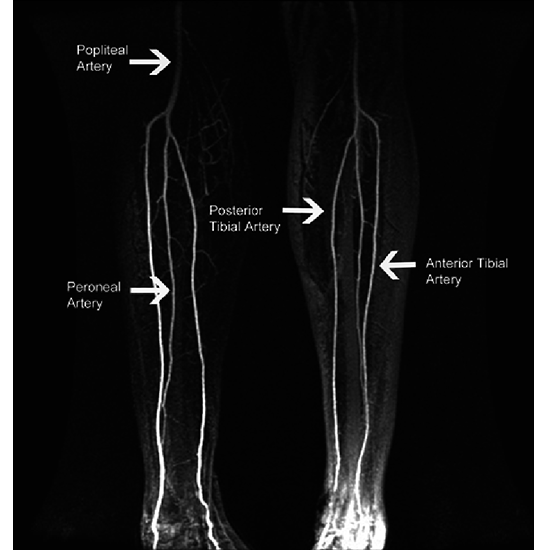

MR Angiography in both lower limbs is the test used to evaluation of blood vessels, in both legs. This is used to check for stenosis and blockage in the lower limbs. MR Angiography in both lower limbs also helps surgeons to better prepare for the surgery.

MR Angiography in both lower limbs test is a Magnetic Resonance Imaging non-invasive medical diagnostic tool used to assess the abnormalities in the blood vessels of both lower limbs.

MR Angiography in both lower limbs test shows blood vessel-related abnormalities in both lower limbs.